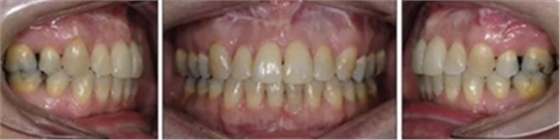

患者曾行正畸治療,現(xiàn)覺(jué)笑容不美觀前來(lái)就診?;颊哒嬗^及側(cè)貌示下頜發(fā)育不足,偏高角,唇閉合不全。上下頜中線(xiàn)齊。覆合、覆蓋4毫米。磨牙關(guān)系及尖牙關(guān)系II類(lèi)。上頜擁擠度4mm,下頜擁擠度6mm。4顆第一前磨牙在第一次正畸治療時(shí)已拔除。上下牙弓呈尖圓型,牙弓狹窄。

患者側(cè)貌改善,下唇唇肌緊張消失,上下唇可自然閉合。磨牙及尖牙關(guān)系糾正至I類(lèi),覆合覆蓋正常。上下頜弓型糾正至卵圓形,牙弓寬度增加。頭影測(cè)量分析示SNA角81.8°,ANB角3°。頭影測(cè)量重疊圖示下頜骨向后旋轉(zhuǎn),垂直面高度略有增加。